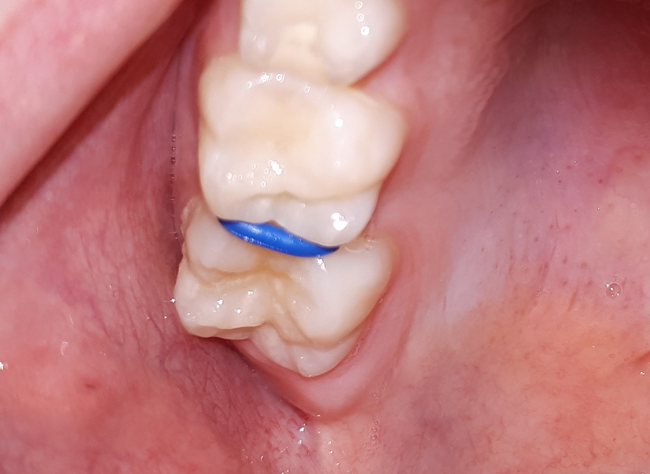

Badanie wizualno-dotykowe powinno być przeprowadzone w stosunku do każdej powierzchni zęba. W ocenie powierzchni stycznych pomocne są elastomerowe separatory ortodontyczne, które rozsuwając zęby, umożliwiają ocenę powierzchni aproksymalnych (ryc. 2).

Ryc. 2. Elastomerowy separator ortodontyczny pomiędzy zębami 16 i 55.